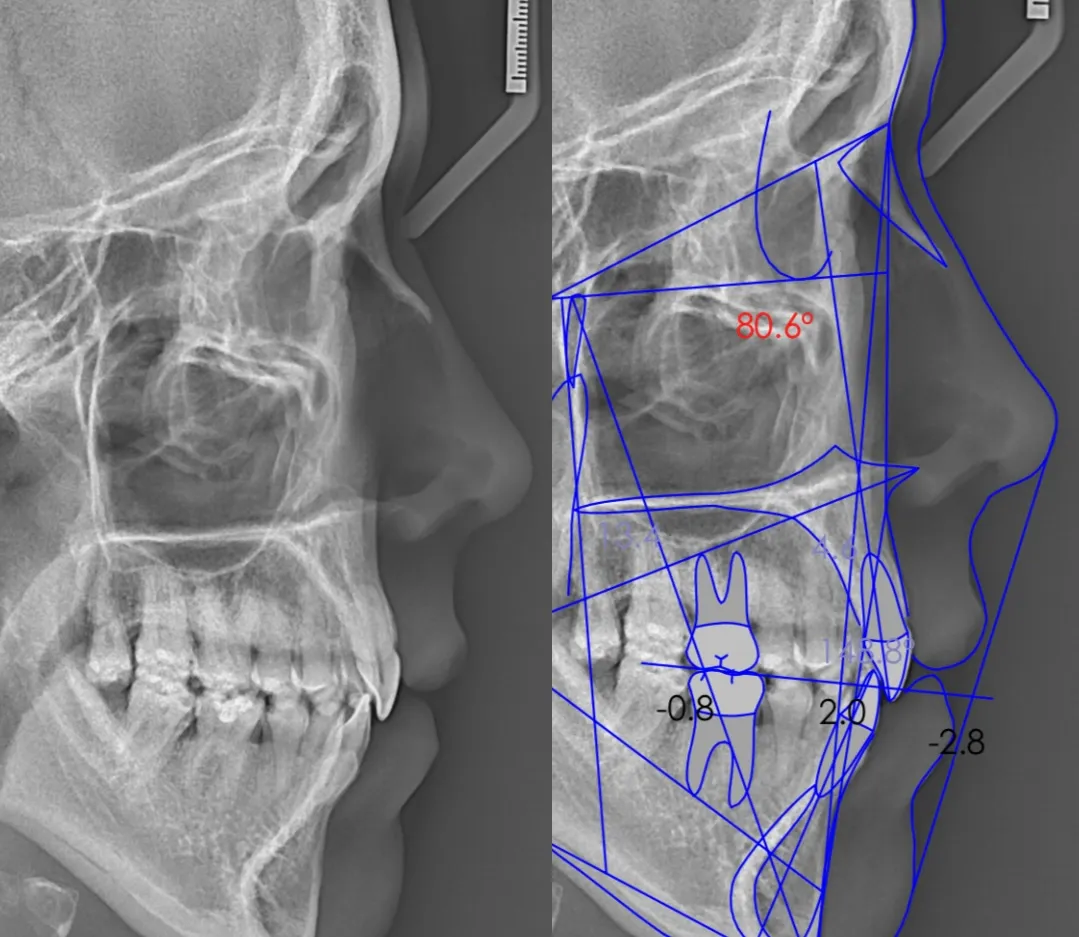

ANÁLISIS CEFALOMÉTRICOS

Nuestros especialistas hacen uso de sistemas de radiología digital de última generación para proporcionarle análisis de ortodoncia y cefalometría de la más alta calidad. Contamos con más de 30 análisis cefalométricos.

PAQUETE ORTODÓNTICO

Incluye: 02 Radiografías (panorámica y cefalométrica), fotografías extraorales, informe cefalométrico del análisis que se solicite (hasta 03 análisis).

PAQUETE ORTODÓNTICO 3D

Incluye: 02 radiografías (panorámica y cefalométrica), fotografías extraorales e intraorales (17 fotos), informe cefalométrico del análisis que se solicite (hasta 03 análisis), escaneo intraoral e impresión 3D.